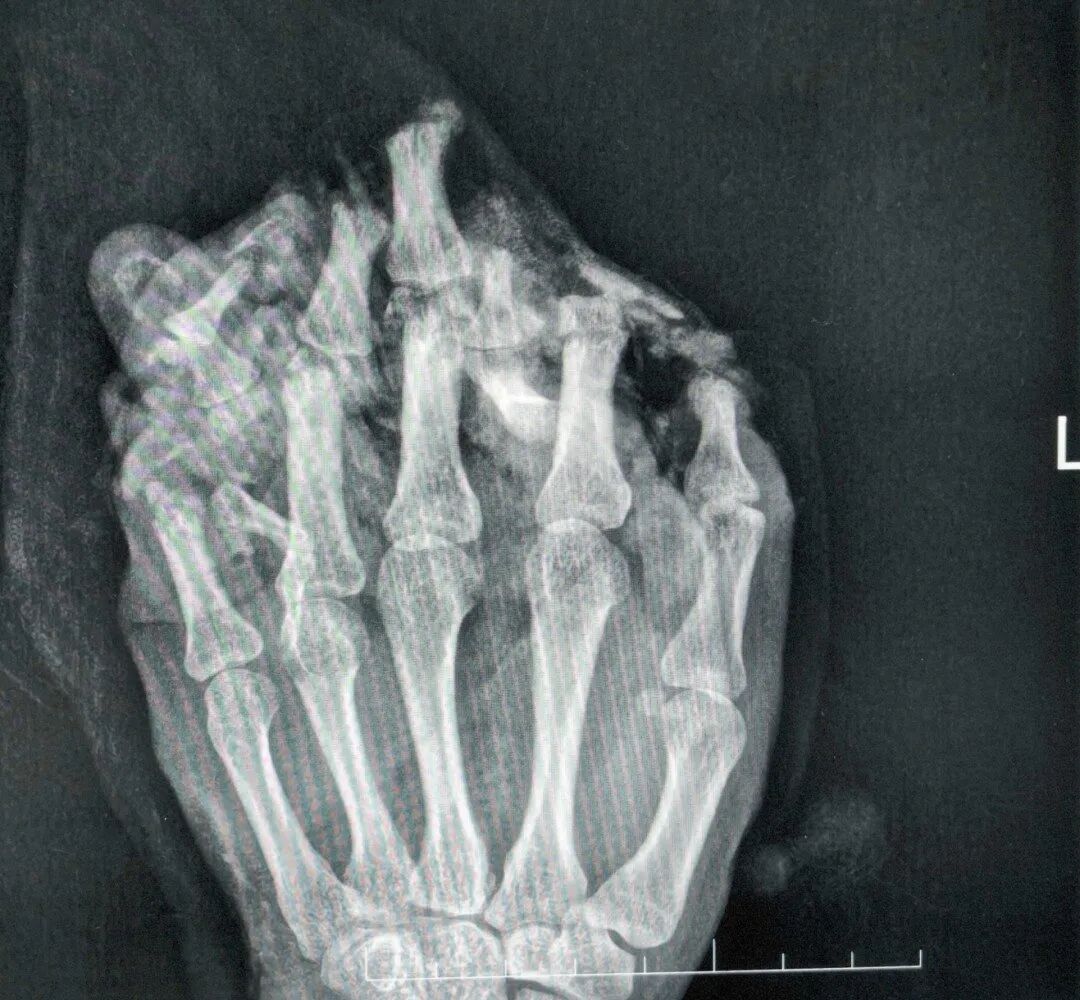

医生诊断他为:1.左手掌、手背,示指中指环指小指掌侧及背侧皮肤毁损脱套伤;2.左手掌、手背及各指肌腱神经血管损伤;3.左手多发性开放性指骨骨折伴毁损;4.左拇指末节指腹皮肤、软组织缺损;5.左拇指固有神经断裂;6.左拇指甲床裂伤。

经过近一个月的“腹手相连”,皮瓣在手部建立了新的血运。医生们进行了“断蒂”手术,让手从腹部独立,患者也获得了活动自由,为功能锻炼打下基础。等待皮瓣完全稳定后,医生们开始了功能重塑。手术将臃肿的皮瓣进行修薄塑形,并进行了首次分指术,把粘连在一起的手指分开,同时取出了已愈合的骨折内固定物。

完美的指蹼(手指间的缝隙)是手指灵活张开与并拢的关键。为进一步改善外观与功能,今年1月11日,医院为他实施了二次分指与指蹼重建术,使用更精密的局部皮瓣,重建出更自然、更深的指蹼,让每根手指都能更独立。